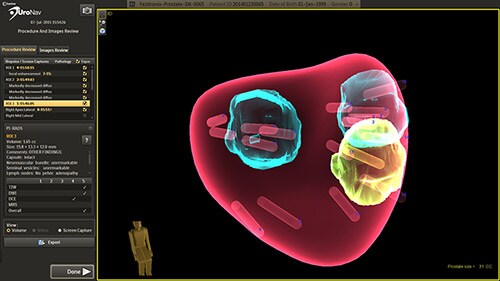

UroNav is an image-guided stereotactic biopsy system used to detect prostate cancer within patients as an alternative to current blind or blind systematic biopsies. It uses multi- parametric magnetic resonance (mpMR) imaging, fused with live ultrasound (US) guidance in conjunction with electromagnetic (EM) tracking to plan, guide, and document prostate biopsies. UroNav simultaneously displays registered MR and ultrasound images and the projected needle path relative to the suspicious target lesion during the biopsy procedure and guides the urologist in real-time.

This novel approach has the ability to improve the sensitivity and specificity of prostate biopsies. This results in a reduced incidence rate of false negative biopsy results. Conventional biopsy or “blind” procedures have a far lower cancer detection rate, which affects patient outcomes by delaying diagnosis, treatment intervention, and limiting treatment options. By enabling earlier diagnosis, UroNav allows a broader array of treatment options to be considered by the clinician, less complications for the patient, and a more cost-effective resolution for the care provider. From set up to post-biopsy review, UroNav guides you through its intuitive workflow. After a quick initialization of the navigation system (upper image), UroNav creates a 3D ultrasound volume from a standard 2D scan of the prostate (lower image).

¹ Pinsky PF, Black A, Parnes HL. Prostate cancer specific survival in the Prostate, Lung, Colorectal, and Ovarian (PLCO) Cancer Screening Trial. Cancer Epidemiol. 2012 Dec;36(6):e401‐6. ² Schröder FH, Hugosson J, Roobol MJ. Screening and prostate‐cancer mortality in a randomized European study. N Engl J Med. 2009 Mar 26;360(13):1320‐8. Images courtesy of Long Island Jewish Medical Center, USA